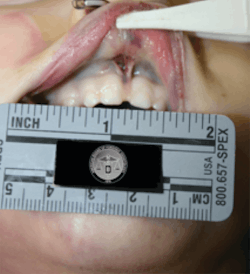

In addition to your clinical diagnosis or differential diagnosis, some additional documentation is recommended here. Take photos (intra- and extraoral) using a ruler or scale next to injuries to show size. Even a cotton roll or periodontal probe can be used, because it is a size that is reproducible and consistent. Coins have been used in some cases for a size reference because that was all that was on hand, and it works! Include quoted remarks, comments, explanations made by the child and by the parent/guardian/caretaker, and take very descriptive notes on hard-and-soft tissue findings and any comments on the observable demeanor of the child and adult. Remember that this might be the only chance to document an injury before it heals.